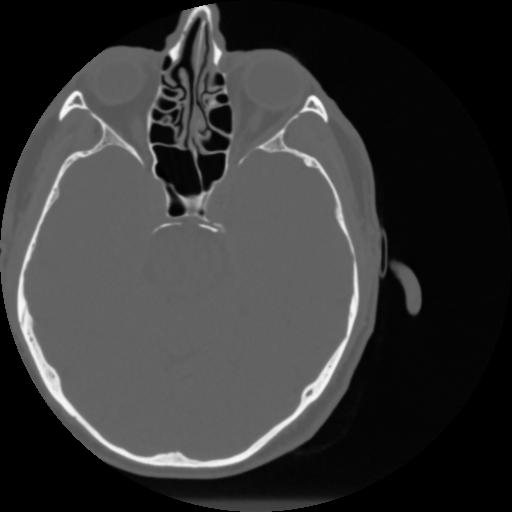

4 CEREBRO,,Vol,0.5,CEREBRO,,